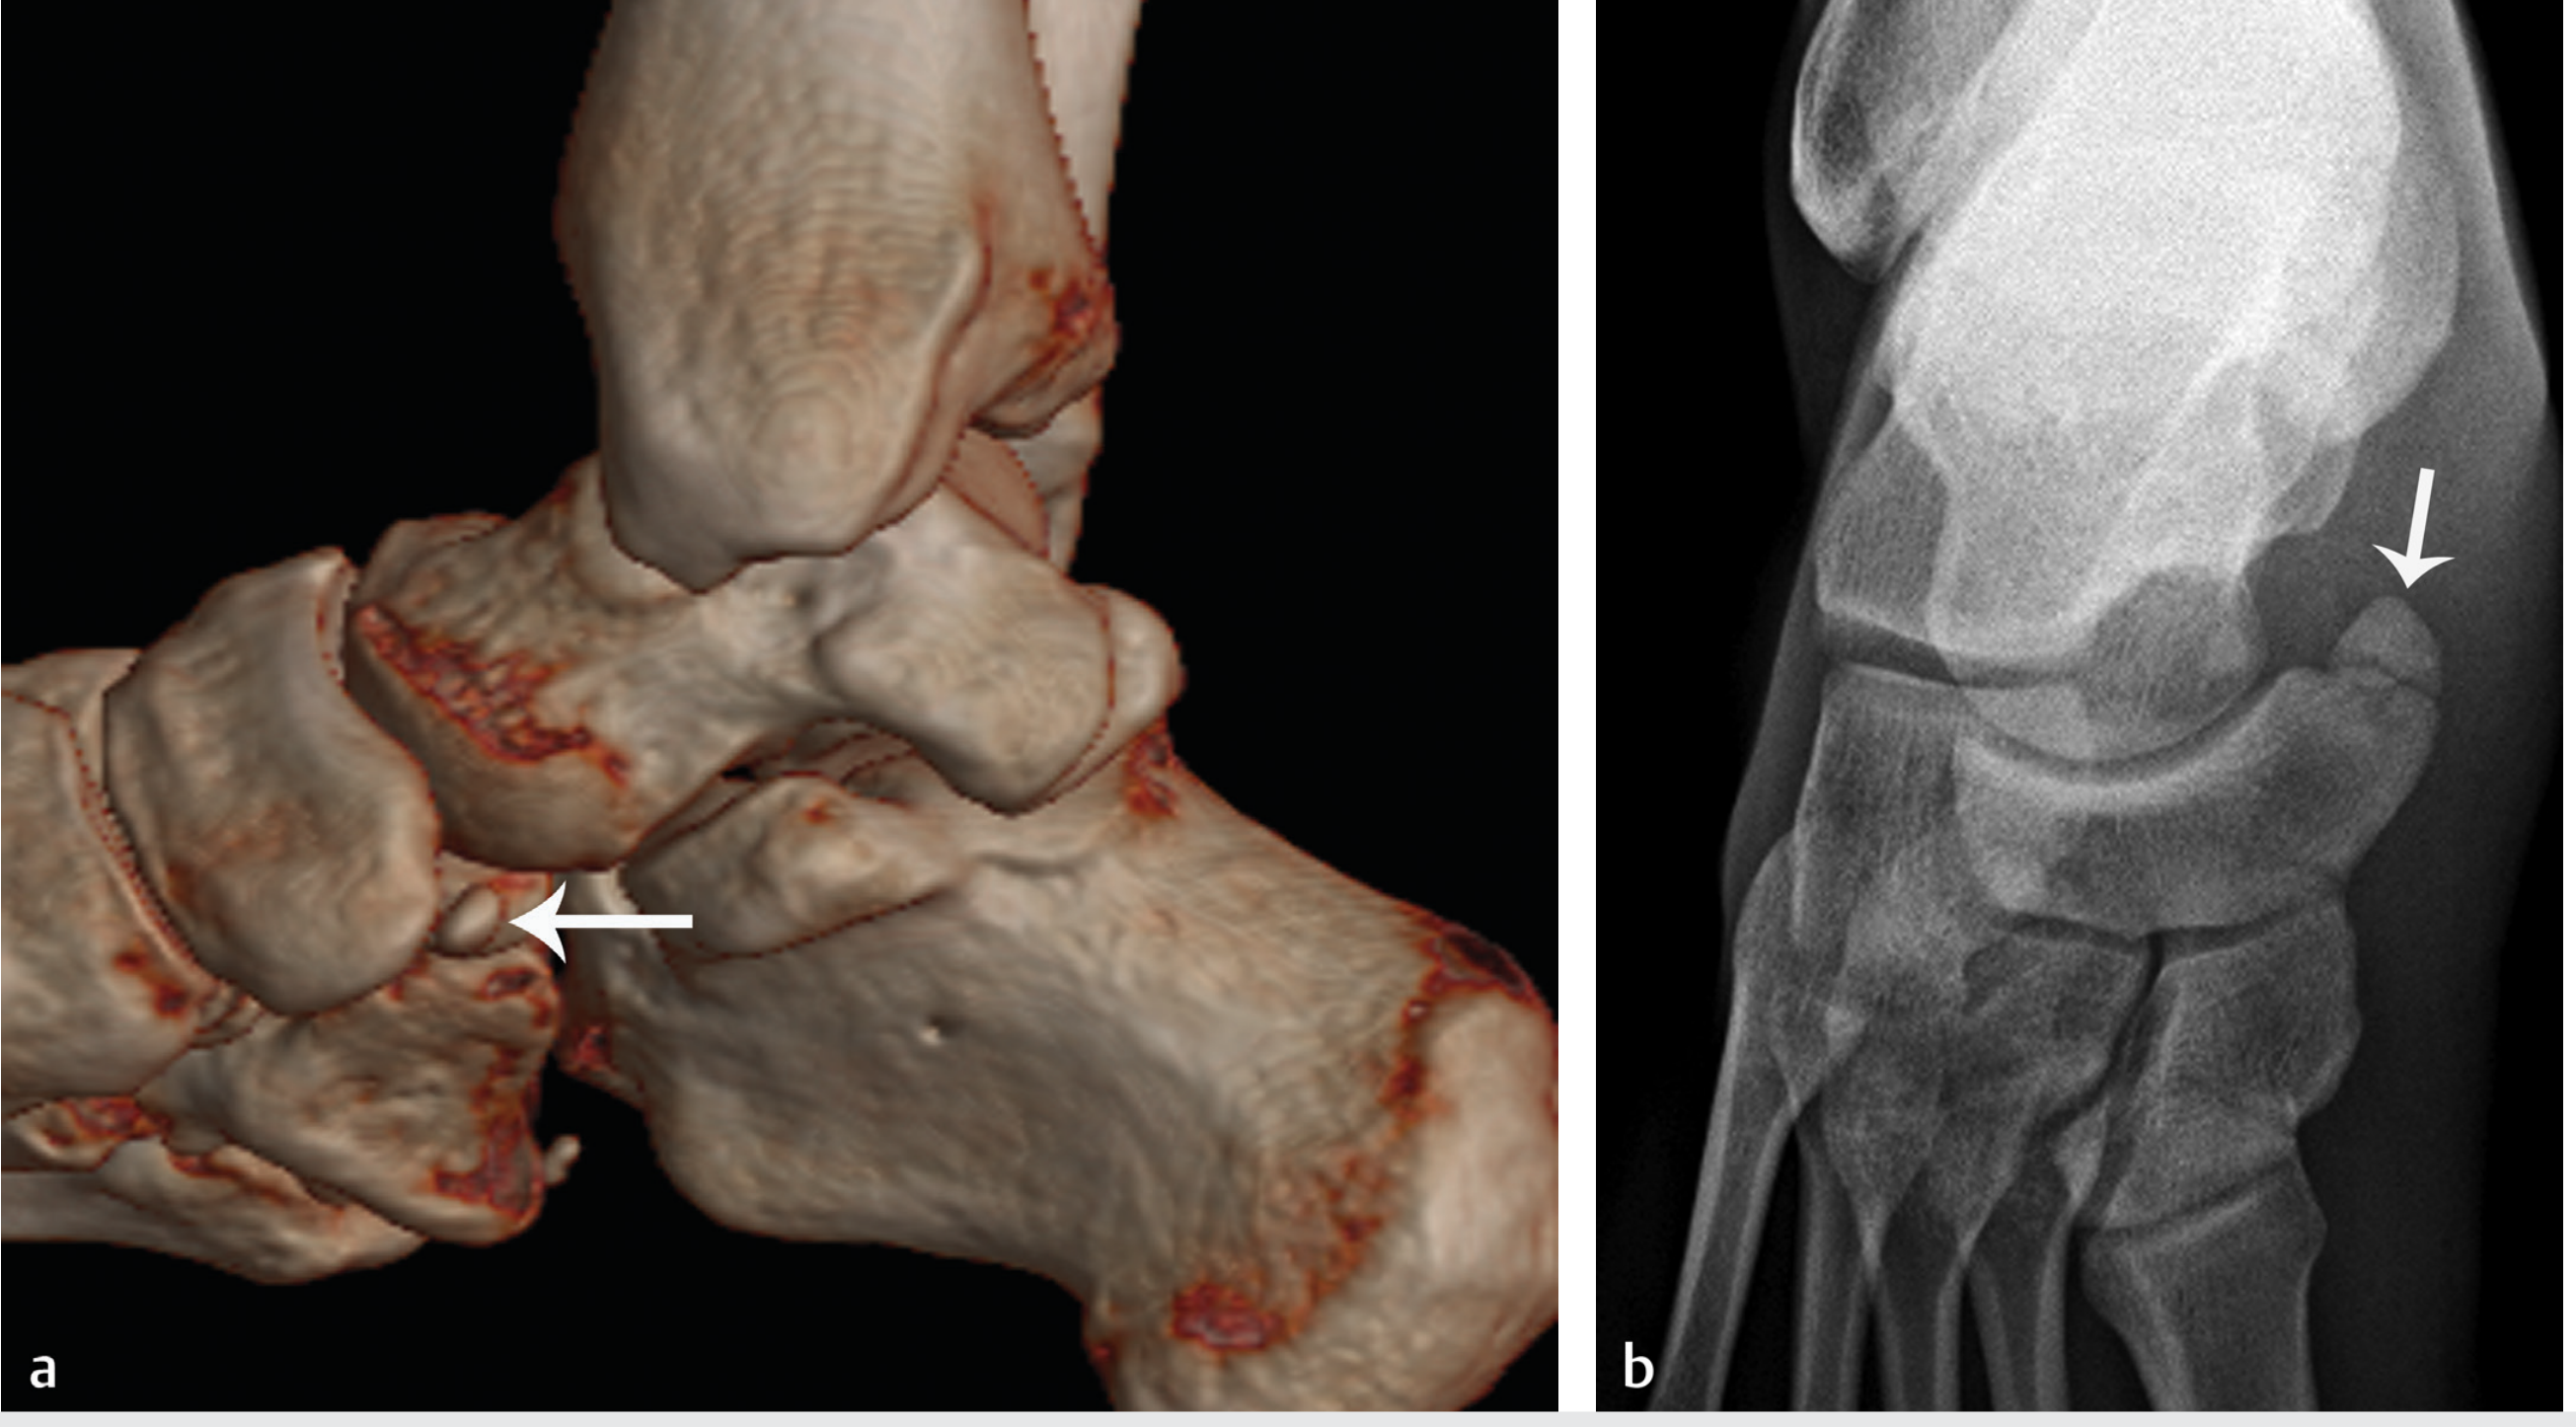

Accessory navicular

| Type 1 | Small sesamoid-like ossicle, no articulation with navicular (likely a true sesamoid); incidental finding |

| Type 2 | Larger ossicle connected to the navicular tuberosity by a fibrous/fibrocartilaginous union (synchondrosis/syndesmosis); most symptomatic type — instability of the synchondrosis causes pain |

| Type 3 | Osseous fusion to the navicular, creating a "cornuate navicular"; may be prominent and cause shoe friction |